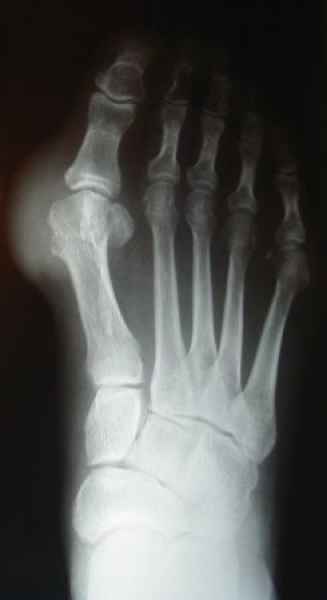

La marcha no solo es característica de la especie humana sino también de cada persona, y más aún varía según el estado de ánimo del momento. Una patología en los pies, se traduce en el rostro, en el ánimo, en el psiquismo. No sólo el dolor produce estos efectos, también un pie deformado o poco estético. En nuestra sociedad, la estética constituye un valor muy apreciado y estas alteraciones causan vergüenza fundamentalmente en las mujeres, que esconden en la playa sus pies en la arena y no pueden usar calzados elegantes.